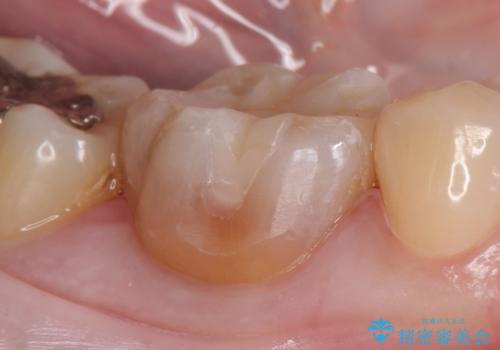

- 右下6番目の歯の舌側に虫歯があるので治療して欲しいといらっしゃった方の症例です。

古い銀歯及び虫歯を除去後、セラミックインレーにて修復を行いました。

当院のセラミックインレーはemaxという強度と審美性に優れた材料を使用しています。

またプレス方式でインレーを製作しているため、削り出しで製作するCADCAMより優れた適合性も持ち合わせており、虫歯が再発しにくい修復物です。